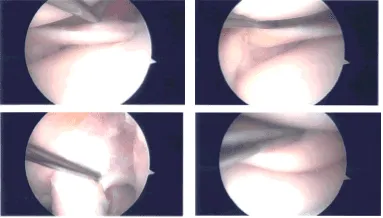

Se creó un portal de entrada lateral e insertó un artroscopio. Se realizó un portal de entrada medial con el uso de una aguja espinal. El examen de la rodilla mostró cambios artríticos en la cabeza femoral medial, así como desgarros del menisco medial a lo largo del cuerno anterior.

No se encontró desgarro en el cuerno posterior, raíz posterior ni en el cuerpo posterior del menisco medial.

El desbridamiento del menisco medial del cuerno anterior se realizó mediante afeitadora. También se realizaba condroplastia del cóndilo femoral medial con el uso de una afeitadora. El examen de la muesca intercondilar mostró LCA intacto con degeneración.

El examen del compartimento lateral y tibiofemoral mostró el menisco lateral intacto, así como el compartimento tibiofemoral bilateral. El examen del compartimento patelofemoral mostró osteoartritis de la troclea de grado 3 a 4, así como la superficie inferior de la rótula.

El desbridamiento de la articulación patelofemoral se realizó mediante afeitadora. La condroplastia por abrasión también se realizaba con la rasuradora tanto a lo largo como en la rótula. Se tomaron las fotos finales por seguridad. La rodilla estaba completamente irrigada.

Imágenes de artroscopia intraoperatoria